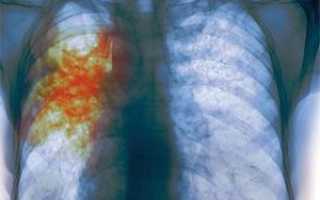

Начальные симптомы болезни включают в себя усталость и кашель, которые сохраняются более трех недель. Со временем в мокроте может появиться кровь, а также возникает дискомфорт при дыхании, поскольку легочные ткани начинают повреждаться. Появление этих признаков требует немедленного визита к врачу.

Начальная стадия туберкулеза у 10-15% больных не проявляется. Обнаружить ее можно только на снимке флюорографии. У 1/3 заболевших наблюдаются симптомы функционального характера, каковыми являются быстрая утомляемость, слабость, снижение работоспособности, повышенная раздражительность.